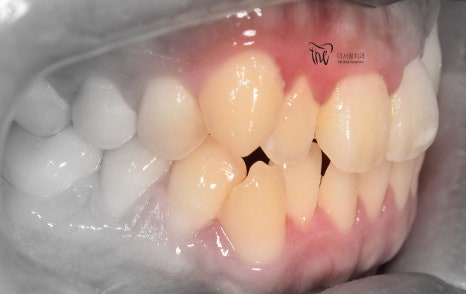

정면 및 측면에서 봤을 때, 측절치의 후방위치에

따라서 반대교합 형태를 보여주고 있으면서

이 때문에 송곳니가 더 덧니처럼 보여지는 느낌을

받고 있는 모습을 볼 수 있습니다.

나아가, 하악의 전치부 쪽에도 총생 현상이

같이 관찰이 되면서 이런 비심미적인 요소들을

개선시키고 싶은 마음으로 더서울치과에

내원하셨던 분입니다.